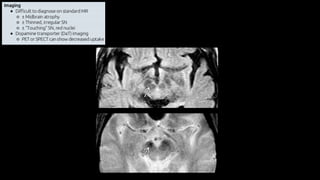

Doença de Parkinson

• Doença neurodegenerativa multissistêmica

• Parkinsonismo: Tremores, bradicinesia e rigidez

• 75% Doença de Parkinson

• Parkinson + demência = Demência da doença de Parkinson

• Parkinson + outros = Parkinson Plus

• Clínica

• Desordem neurodegenerativa

• Histopatologia

• Doença de corpos de Lewy

• Imunohistoquímica

• Sinucleinopatia

Introdução

• Etiologia

• Degeneração de neurônios dopaminérgicos (60%)

• Redução da dopamina no corpo estriado (80%)

• Idade

• Genética

• Patologia

• Atrofia mesencéfalo, com formato em “borboleta”

• Despigmentação da substância nigra

• Presença de corpúsculos de Lewy

• Tratamento

• Levodopa

• Sistema de estimulação cerebral profundo (DBS) no núcleo subtalâmico